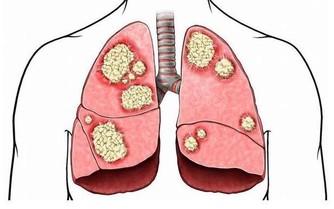

不要小看便秘,這也影響著我們的美麗,更影響著我們的健康。中醫認為「六腑以通為順」,便秘可以導致腑氣不通,進而影響全身氣機的運行及五臟的變化。《內經》中說:「魄門為五臟使」。魄門就是指大腸,意思就是說大便的通與不通直接關係著五臟的功能運作,關係機體的整體狀況。